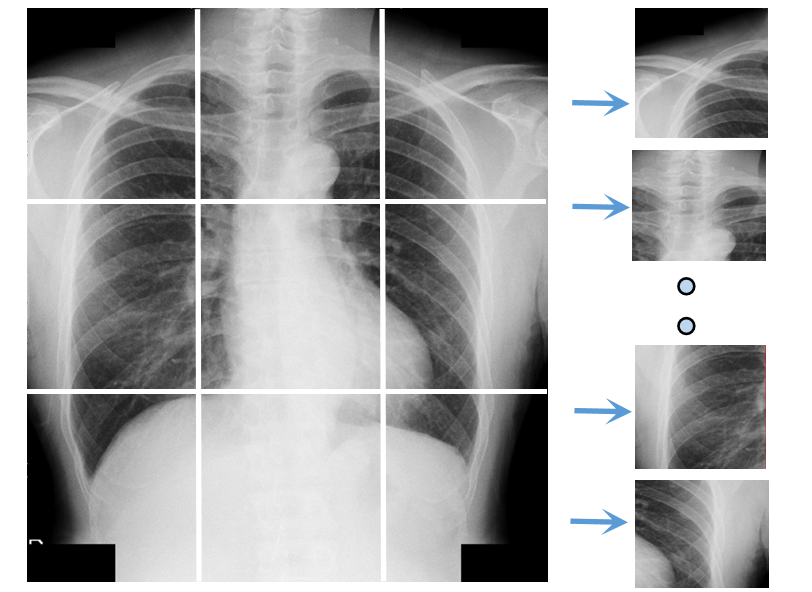

As the first step in the proposed pipeline, bone selection and region cropping prepare the model inputs. There are multiple bones in the chest area, bearing varied importance for BMD prediction. Although all bones provide density information due to the metabolic nature, the model should focus on the most effective regions. It is also unclear if the combination of distinct bone patterns are essential for this task. To learn representations of the local textures and to explore the correlation among different regions, medical experts advise us to extract ROIs for clavicle bone, cervical vertebra, lumbar vertebra, ribcage edges. We avoid the central part of the chest X-ray where cardiac or pulmonary diseases may significantly influence the appearance. In the end, our model works on the ROI croppings of left/right clavicle bones, cervical spine, left/right rib-cage area, T12 vertebra.

We employ the Graph Convolution Network (GCN) based Deep Adaptive Graph (DAG) [40] to automatically detect critical landmarks in the chest. We identify 16 landmarks in Figure 1, which include 1) 3 points on the left/right clavicles, 2) 4 points along the left/right rib cages, 3) 1 point on the C7 vertebrae, 4) 1 point on the T12 vertebra. We manually labeled 1000 cases (16 landmarks on each CXR scan) as the training samples for the DAG model. The resulting landmark detector can reliably extract all the keypoints. Given the keypoints for each bone, we crop the corresponding bone regions. However, different bones have distinct shapes and sizes, so we further sub-split the wider and higher ones. As seen in the cropped ROIs 1, there are 2, 2, 4, 4, 1, 1 croppings for left clavicle, right clavicle, left ribcage, right ribcage, cervical, lumbar respectively. This arrangements are based on the bone size and width/height ratio. Besides these 14 local ROIs, we also include the whole CXR image as one modality. These 15 ROIs are resized and normalized before going through CNN layers.